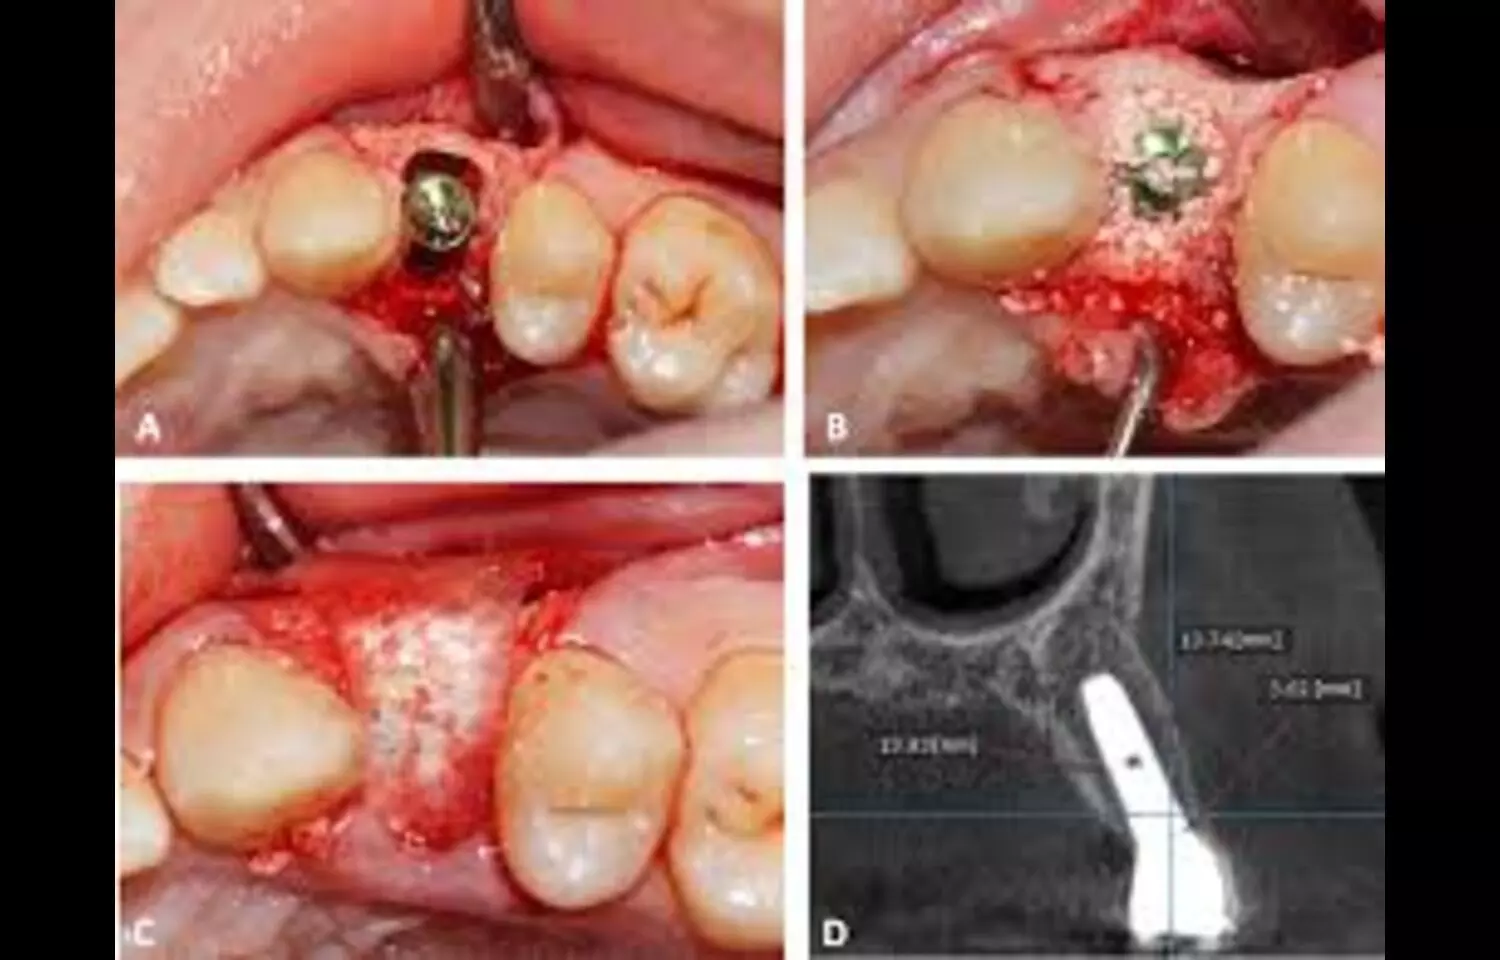

During immediate dental implant placement, regenerative materials are often used to fill the peri-implant space following tooth extraction and implant insertion. One such material gaining popularity in contemporary dentistry is platelet-rich fibrin (PRF). This study aims to examine existing scientific literature to determine if PRF effectively promotes the filling of the peri-implant gap and regeneration of soft tissue in single-unit immediate dental implant placement compared to alternative materials. The systematic literature review was performed according to PRISMA guidelines. Databases searched included PubMed, Cochrane Library, ScienceDirect, Google Scholar, Scopus, and ResearchGate, up to November 19, 2024. Selection criteria included studies on humans, written in English, and using PRF for the management of the peri-implant gap in immediate implantation. Seven publications were reviewed: 2 studies compared PRF with blood clots, 2 with collagen and bone substitute, and 3 with bone substitute alone. Implant stability quotient results in slightly favoured PRF over blood clot and collagen with bone substitute, although results were inferior to bone substitutes alone. One study noted significant crestal bone improvement with PRF versus collagen and deproteinized bovine bone (DBB). One study reported higher resorption in the PRF group compared to DBB and beta-tricalcium phosphate at the buccal site. Control groups generally exhibited lower peri-implant pocket depths, though no significant differences were observed between groups across studies and follow-up.

PRF effectively promotes regeneration of the peri-implant hard and of soft tissue in single-unit immediate dental implant placement compared to control groups, although no significant differences were observed between alternative materials across studies and follow-up.